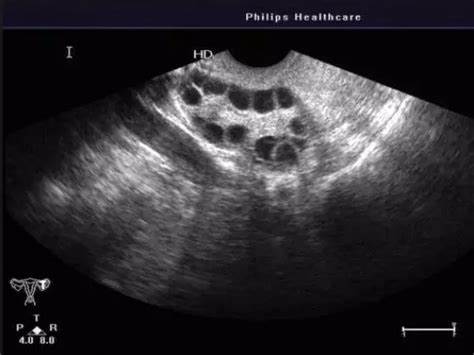

多囊查基础卵泡数量是做b超还是阴超更准确些呢?

做阴超,因为阴超是将超声探头放入患者阴道进行观察和诊断,和B超相比不会受到腹壁厚度影响,而且不需要憋尿,能够减轻憋尿痛苦,最主要的是由于阴超更接近子宫和卵巢,所以成像清晰,分辨率也很高,所以检查出来的结果也会更加的准确,如果大家想去查基础卵巢数量的话建议选择阴超。正常情况下,女性每个月会有3-11个基础卵泡,而随着年龄的增长,数量会逐渐下降,卵泡数量越少、自然怀孕率越低,所以基础卵泡数量与年龄是息

月经后三天阴超监测卵巢一侧有10多个卵泡算是多囊吗?

一侧卵巢有10多个卵泡并不一定算是多囊卵巢综合征。多囊卵巢综合征的诊断需要综合考虑多个方面的因素,包括月经异常、高雄激素血症、卵巢形态学表现(如卵巢体积增大,卵巢内直径2-9mm的卵泡数≥12个),以及排除其他可能引起高雄激素和排卵异常的疾病等。因此,月经后三天阴超监测到一侧卵巢有10多个卵泡,并不能直接诊断为多囊卵巢综合征。随着环境和生活方式的改变,多囊卵巢综合征(PCOS)已成为一种常见的妇科